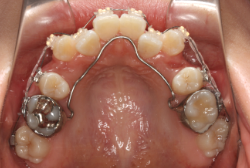

診断の結果、典型的なアングル2級1類の上顎前突です。上下歯列の正中の不一致も見られます。しかし、歯の大きさは平均値に近く、配列の凸凹がそれほど見られません。このまま放置すると、将来的には抜歯を伴う矯正治療を行う可能性が高くなりますが、このタイミングで適切な治療をすると、非抜歯治療が可能かもしれません。

矯正歯科医が着目するのは、奥歯の噛み合わせの位置関係です。前歯の位置にそれなりの差が生じていても、奥歯の位置が正しければそれほど重症という評価にはなりません。このケースの場合は、上下の第一大臼歯の位置関係は、直線的に一致しているタイプでした(矢印が一致)。混合歯列時期の奥歯の位置関係としては、ほぼ正常な状態といえますが、症状から言うと、上の奥歯をもっと後ろに下げてやることができれば、上顎歯列全体に余裕ができるので、凸凹も解消できるし、前歯の傾きを内向きに修正することもできると考えられました。しかしこのまま全体に永久歯が生えきってしまうと、上の前歯が出たままになってしまいますので、生え替わりが完了する前に大急ぎで奥歯を後ろに下げる必要があると判断しました。

こういう症状でもっとも効果があるのが、顎外固定装置と言って、お口の外部から奥歯に力をかける方法です。 写真の装置はネックバンドというタイプの装置です。この装置は取り外し式ですので、夜寝るときに毎日自分で取り付けて、寝ている間に少しずつ上の奥歯を後ろに下げていきます。この装置には、奥歯を後ろに下げる効果だけでなく、上顎の過剰な成長発育の抑制、下顎の成長促進作用があるとされており、上顎前突の症状にはいずれも有利な効果が期待できます。

ネックバンドを1年半使用して、上顎大臼歯が十分後ろに下がったところで、裏側にリンガルアーチという固定のワイヤーを取り付けて、新しく生じた隙間が狭くならないよう「保隙(ほげき)」という処置をして、永久歯が生えそろうまで待機中の様子です。配列全体に隙間が生じているのがお分かりいただけると思います。これだけの隙間が確保できていれば、抜歯をしなくても、あとで上の前歯を内側に理想的な角度で引っ込めることができます。このように完全に永久歯列になる前に、十分な隙間が確保できるかどうかが、非抜歯で矯正できるかどうかの分かれ目になります。

初診時と違い、上の奥歯がより後方に下がっていることが分かります。ただしこの段階では奥歯は後ろに下がりすぎの状態です。しかし次の段階でマルチブラケット法を始めると、上の奥歯は次第に前にズレて来ます。最終段階で正しい位置にするためには、この段階では余分に後ろに下がっている必要があります。

第2段階としてマルチブラケット法を非抜歯で1年間行いました。歯の傾斜が修正され、正中も一致し、美しく機能的な配列に仕上がりました。再診時に確保した隙間をすべて使って、すべての永久歯を理想的な位置に配列することができました。前傾していた上の前歯は真っ直ぐに直立し、完全な正常咬合が確立できています。